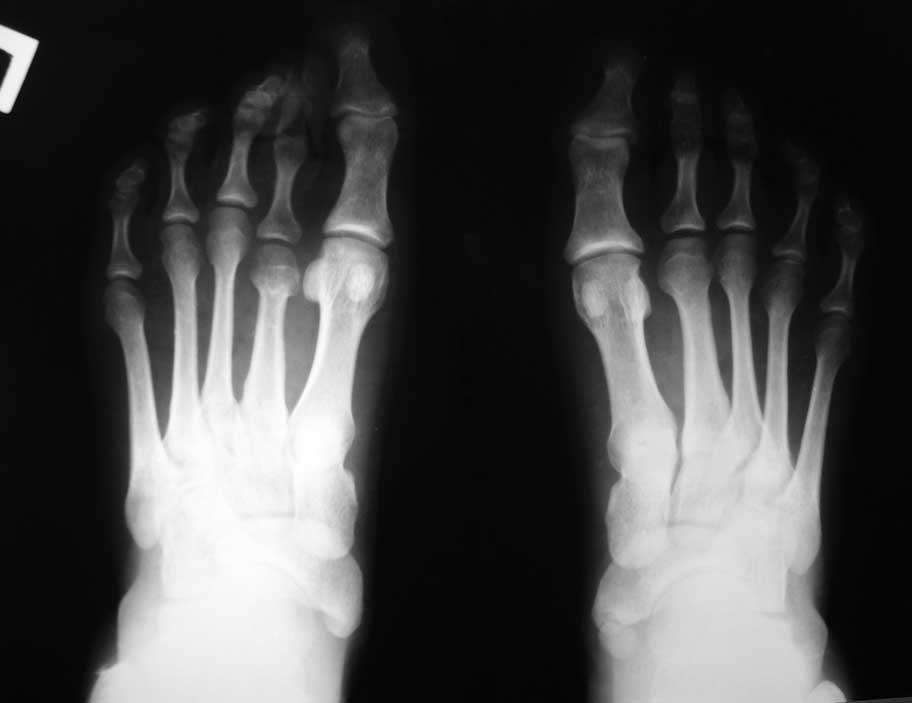

У больной М., 25 лет врожденное укорочение 2 плюсневой кости стопы и, как следствие, 2 пальца в целом.

Палец мешает носить обувь.Имеется тенденция к молоткообразной деформации. Снимки прилагаются. Варианты оперативного лечения?